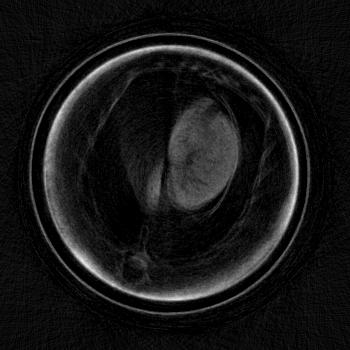

Exemplary for the data, one set of axial cross-sections of the lung region of the second mouse are displayed in Figure 5 (marked as horizontal lines in Figure 4). In all three CT cross-sections, the lung tissue can clearly be located in the chest of the mouse. The location found with the CT reconstruction corresponds with the location visible in the dark field projection image and the speckled area in the differential-phase image. In contrast, the exact position of the lung cannot be located with the absorption image alone.

To quantify the location of lung tissue within the mouse, a CT scan of the second mouse was performed. Its results, shown in Figure 5, substantiate the above results that lung tissue is, indeed, only present in the right part of the mouse’s chest cavity in this cross-section plane. It is imaginable that an assured diagnosis can be made without a computed tomography scan, which could lead to a quickened diagnosis and a dose saving.